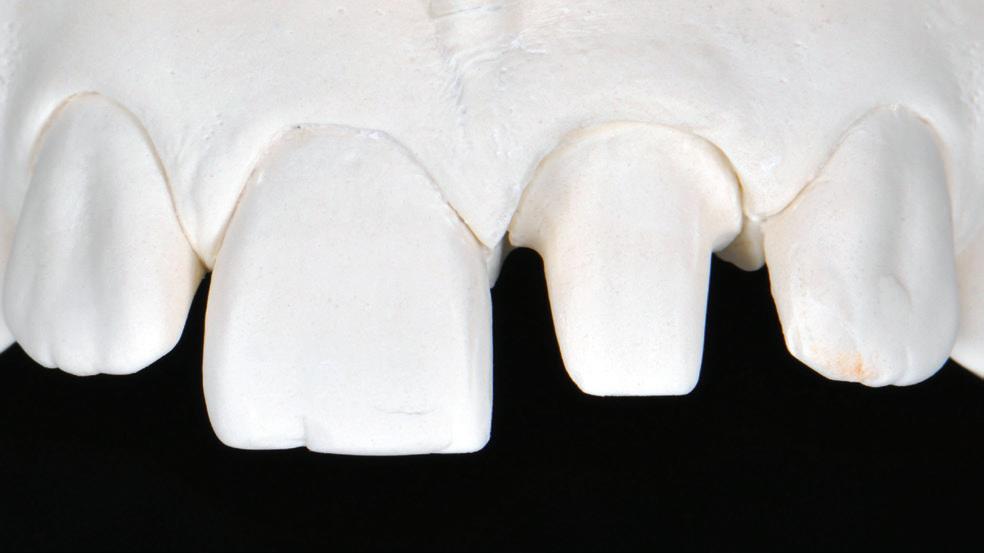

Figure 4. Maxillofacial surgery. Figure 6. TMJ analysis. Figure 8. Airway analysis. Figure 10. Periodontics. Figure 5. Orthodontics. Figure 7. Implant placement. Figure 9. Prosthodontics. Figure 11. Endodontics.